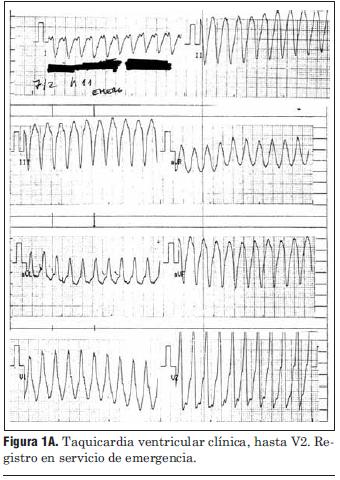

Paciente de 69 años de edad, sexo masculino, procedente del departamento de Tacuarembó. Ingresa al centro de tratamiento intensivo del Hospital de Tacuarembó el día 1º de febrero de 2010. Había consultado horas antes por episodio sincopal constatándose una taquicardia regular de complejos QRS anchos (figuras 1A y 1B), hipotensión arterial y mala perfusión periférica; es medicado inicialmente con adenosina intravenosa, sin respuesta; se resuelve cardiovertir eléctricamente; al administrar propofol i/v revierte espontáneamente a ritmo sinusal.

Figura 1A. Taquicardia ventricular clínica, hasta V2. Registro en servicio de emergencia.